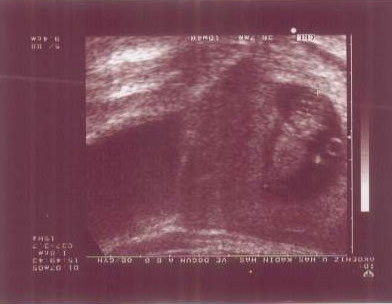

The first ultrasound scan of Ender at 2 months into the pregnancy. |

This is how it all began, Ender's the potatoe-shaped thing on the right. Ender's Mum and Dad (Carl and Zühre) were trying to have a baby for 6 months. We were considering having fertility treatment when I was sent to Lithuania on business for a few weeks. When I got back, I had a short holiday. We didn't do anything special, just stayed around at home; but somehow Zühre became pregnant a month or so after I got back. This is an ultrasound scan of Ender 12 weeks after conception. At this stage we didn't know if he was a boy or a girl (I thought he looked like a potato), but we didn't care ... we were going to have a baby! |